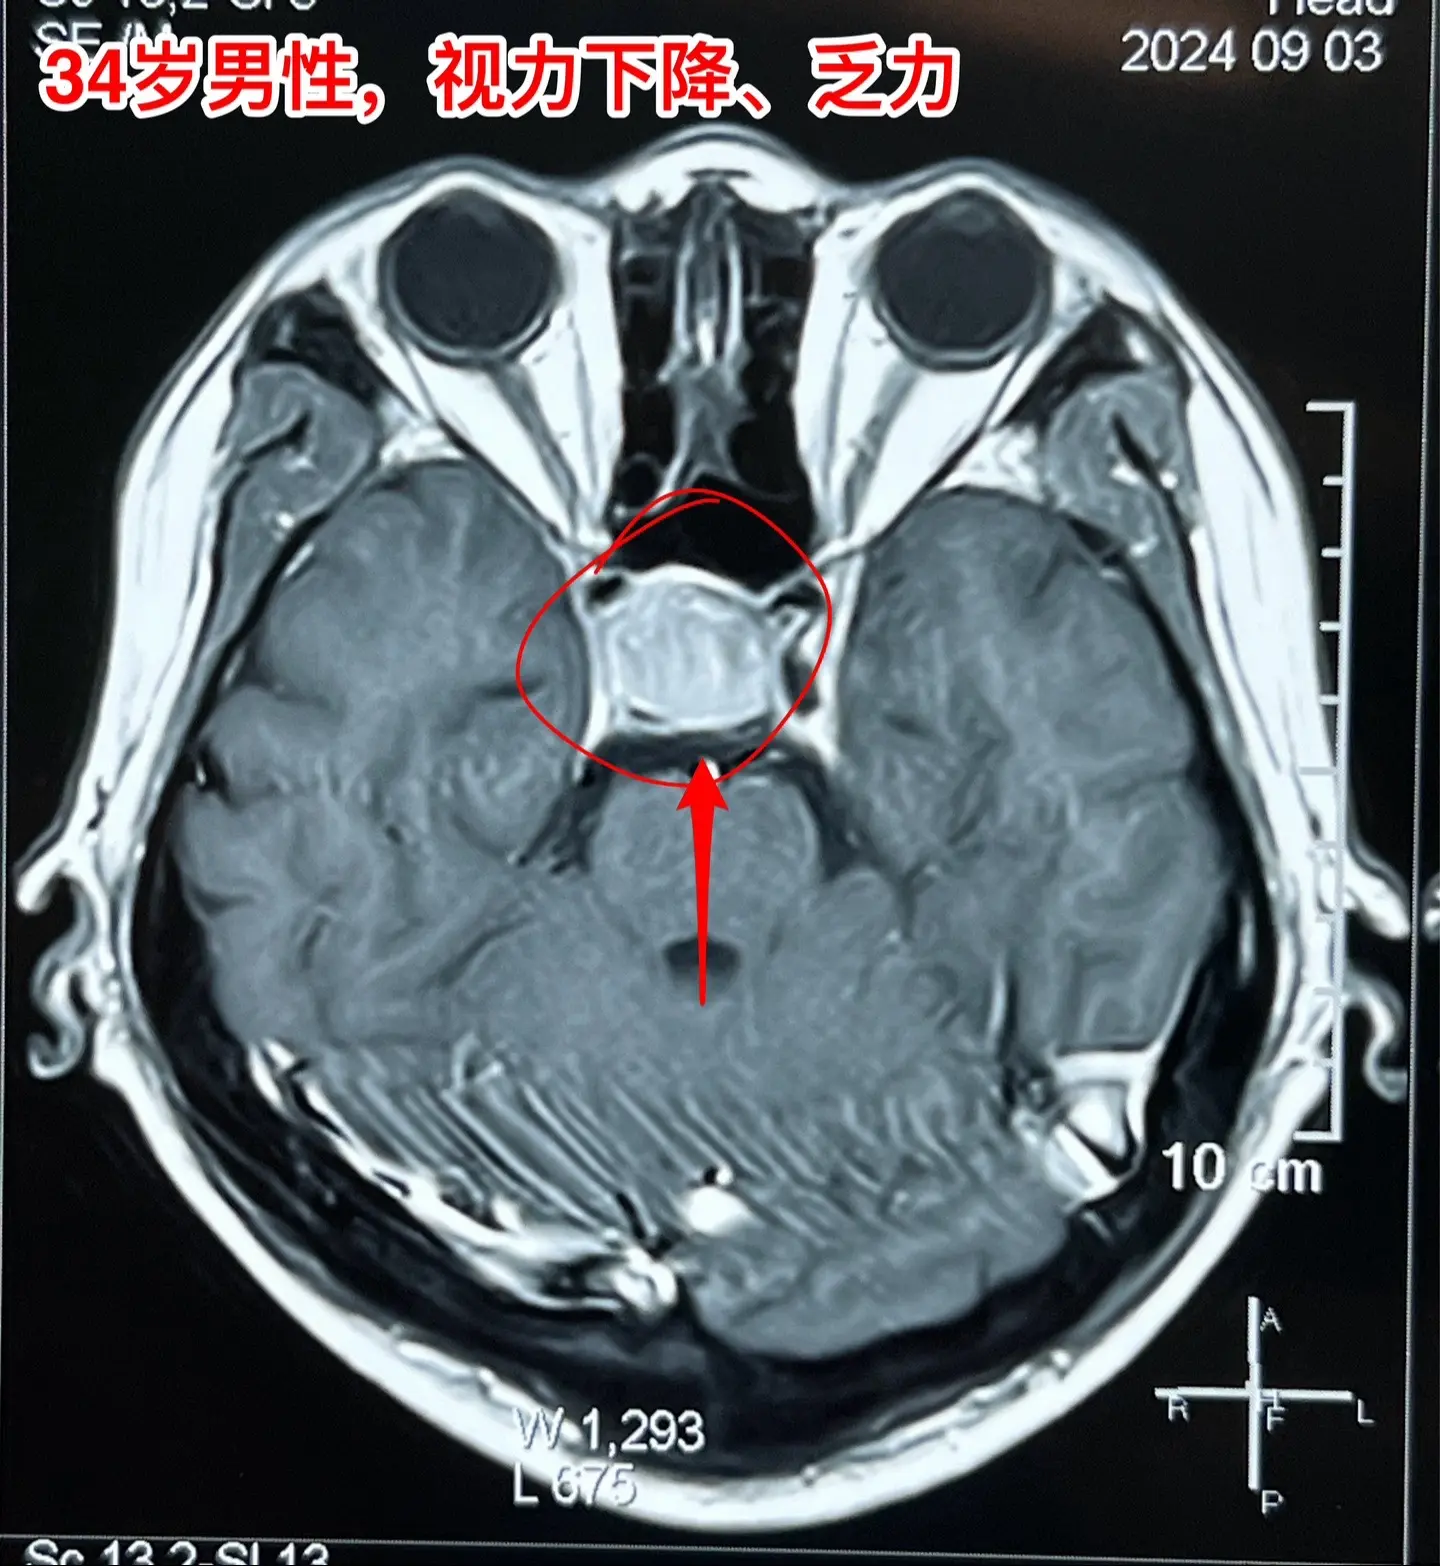

34岁男性视力下降、三个月体重下降30斤。34岁山东滕州男性,视力下降半年,头痛、恶心、乏力4个月,同时食欲不振,三个月体重下降30斤。在当地医院内分泌科住院检查,发现鞍区囊性病变,没有钙化。

这是颅咽管瘤还是拉克氏囊肿?

我们把拉克氏囊肿放在第一位。有时候这两种病还是很难鉴别的。